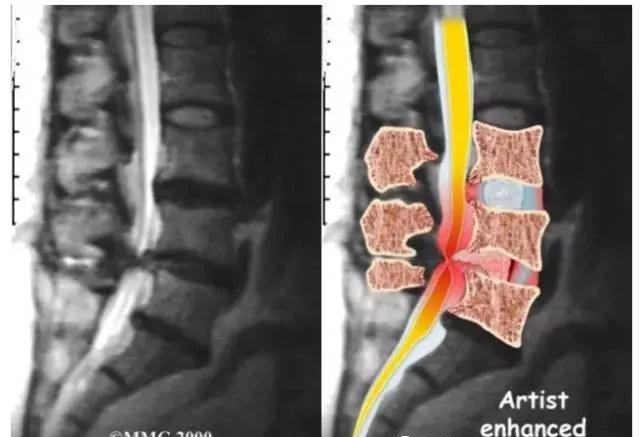

(2)CT,CTM及MRI检查:CT检查可显示椎管及根管断面形态,但不易了解狭窄全貌;CTM除可了解骨性结构外,尚可明确硬膜囊受压情况,目前应用较多,此外,MRI检查更可显示腰椎椎管的全貌,目前大多数骨科医师已将其作为常规进行检查。

(2)CT,CTM及MRI检查:CT检查能显示椎管的断面形状,因而能诊断有无侧隐窝狭窄及有无神经根受压;CTM检查显示得更为清楚,MRI检查可显示三维影像,可同时确定椎间盘退变的程度,有无突出(或脱出)及其与硬膜囊,脊神经根之间的关系等。